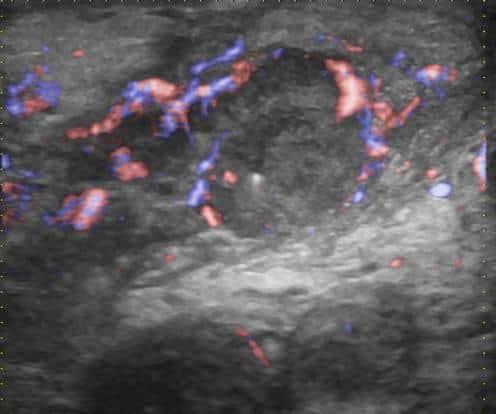

Viêm mào tinh hoàn

» Thông tin: Nam giới – 39 tuổi.

» Lâm sàng: Sưng đau vùng bìu.

# Viêm mào tinh hoàn apxe hóa.